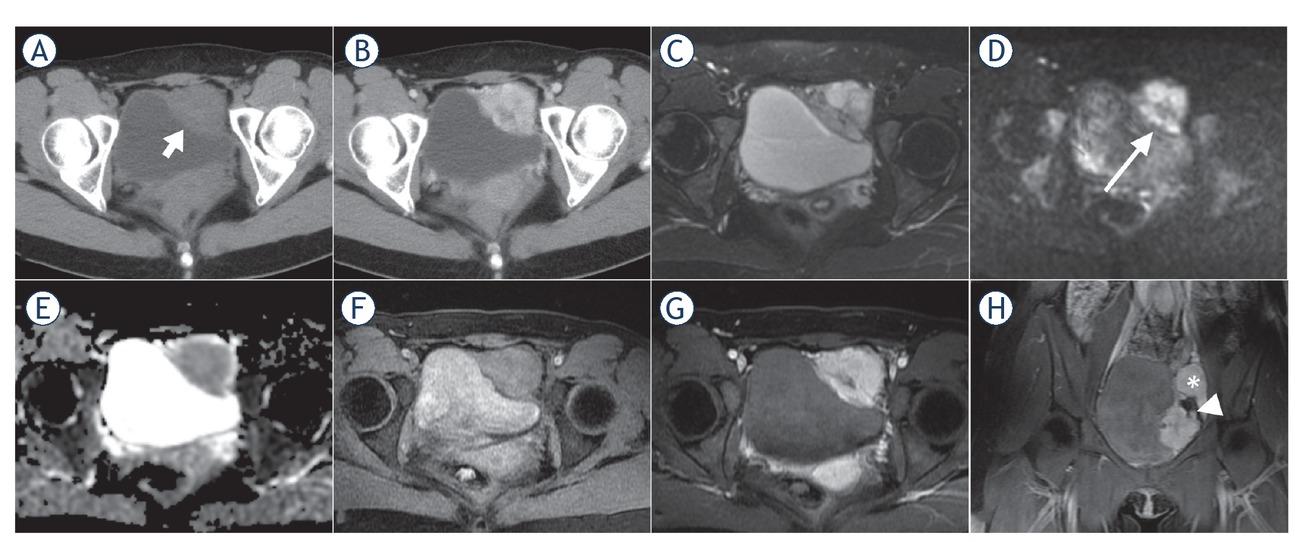

CT and MR images of a 25-year-old female with malignant bladder paraganglioma. The tumour was located in the left bladder wall with irregular shape, presenting heterogenous hypodensity (short arrow) and obvious enhancement on axial pre- and post-contrast enhanced CT images (A, B), heterogenous slight or marked hyperintensity on T2-weighted images (T2WI) (C), heterogenous hyperintensity on diffusion-weighted images (DWI) (long arrow) (D), hypointensity on apparent diffusion coefficient (ADC) maps (mean ADC value, 0.997×10-3 mm2/s) (E), slight hyperintensity compared to the gluteus maximus on T1WI (F) and early marked enhancement on arterial phase images (G). Coronal enhanced MRI showed the lesion encased the left iliac artery branch (arrowhead); a similar enhanced lesion was located next to the left iliac vessels (asterisk), suggesting multiple paraganglioma (H).

On non-contrast CT images, the lesions mainly demonstrated homogeneous and soft-tissue density, with CT values ranging from 19.9 to 55.2 Hounsfield Units (HU). Intra-tumoural cystic degeneration or necrosis was rare (2/16). All lesions showed moderate to marked enhancement in the arterial phase of contrast-enhanced CT images (Table 3), with CT values of 64.3–117.9 HU, which were about 2.3 times that of the CT value on pre-contrast enhanced images (Figure 4A–B). In the two patients with multiple paragangliomas, the density and enhancement pattern of lesions in the non-bladder sites were similar to those in the bladder.

On T2WI, the lesions demonstrated homogenous hyperintensity (10/16), higher than the gluteus maximus and lower than the urine in the bladder, without typical “pepper and salt” sign. Due to the restricted diffusion, the lesions showed hyperintensity on DWI and hypointensity on ADC maps (mean ADC value ± standard deviation, 0.883 ± 0.126×10-3 mm2/s). On T1WI, the lesions showed hyperintensity and averaged 1.4 times higher than that of the gluteus maximus at the same layer. Following MRI enhancement, the BPGs all had obvious enhancement in the arterial phase (an average of 2.5 times higher than the tumour signal intensity on T1WI), slightly decreased enhancement in the venous phase and the delayed phase (an average of 2.4 and 2.0 times higher than the tumour signal intensity on T1WI, respectively), exhibiting a “fast in and slow out” enhanced pattern (Table 3, Figure 4C–D). Similar to CT findings, the two patients with multiple paragangliomas showed comparable MRI findings between the bladder and non-bladder lesions.

Imaging methods are primarily used for localization of the paraganglioma.11 In the absence of typical clinical manifestations and negative biochemical tests, imaging can also be used as a complementary approach for qualitative diagnosis. CT has a high sensitivity (82%) in detecting extraadrenal pheochromocytoma.9 We demonstrated that most BPGs are typically present as a solitary lesion protruding into or out of the bladder cavity, with an oval shape, soft tissue density, well-defined margin and a broad-base attachment to the bladder wall. The tumour exhibits slightly lower density and early marked enhancement on the contrast-enhanced CT images. Contrary to the previous literature, T2WI showed that BPGs are mostly homogeneous and high-intensity, without the typical “pepper and salt” appearance.12,13 The homogenous nature may be due to the fact that the lesion was still small when it was detected, and intratumoural degeneration has not yet occurred. Similar to bladder cancer, BPGs show marked hyperintensity on DWI and hypointensity on ADC maps due to restricted diffusion of water molecules.14 The tumours presented slight hyperintensity on T1WI and “fast in and slow out” enhanced pattern on contrast-enhanced images, which may be distinctive MRI features of BPGs.10,15 The potential pathological bases for the above imaging findings are that the tumour cells are large with abundant cytoplasm and the intercellular stromata are rich in blood vessels showing fissure or haemangiomalike dilatation.16

The malignant rate of BPGs is estimated to be 10–15%.9 Because no reliable pathological evidence exists for early differentiation between benign and malignant tumours, direct invasion of adjacent tissues or distant metastases are considered to represent potential malignancy.17 In this study, two lesions showed features of peripheral tissue invasion, suggesting malignancy. At present, dynamic contrast-enhanced MRI incorporating non-fat suppression T2WI with small FOV and high resolution, by means of the natural contrast between pelvic fat and urine in bladder, is the preferred imaging method for recognition of possible malignant tumours.18 In addition to CT and MRI, functional imaging is recommended to detect multi-focal and metastatic disease, such as 123I-metaiodobenzylguanidine (123I-MIBG) SPECT and 68Gallium-labeled somatostatin analogues (68Ga-DOTA-SSA) PET/CT. Depending on specific ligands that target specific cell membrane transporters or vesicular catecholamine transport systems, this modality can provide greater diagnostic specificity.12,19